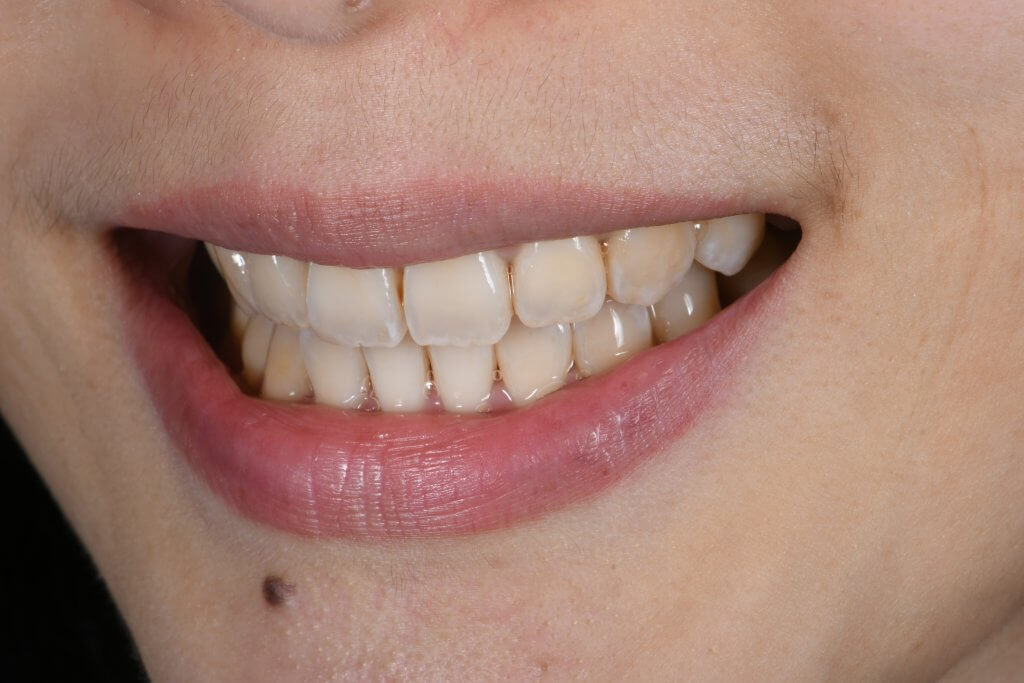

骨性暴牙案例:改善嘴突、笑齦與深咬的綜合治療

- 主要訴求: 改善下排齒列不整齊、中度深咬以及嘴突感。

- 臨床矯正分析: 患者具備明顯的骨性暴牙特徵(更多介紹可參考此文)。上顎骨骼過度向下生長導致笑容時牙齦露出量過多(笑齦),且伴隨中度深咬問題,增加了後收門牙的難度。